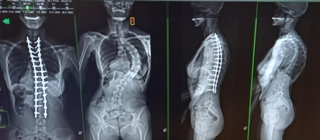

I went to see my doctor because of the intense pain I was experiencing in my back and down my legs. Seeing the x-rays of my spine, I was dumbfounded at the degree of curvature. The 91-degree protruding curve gave me trouble, as I was constantly irritating it by bumping against things. However, to my surprise, my doctor said that I had to have both hips replaced before the spinal surgery could be done.

My maximum height had been 5-feet 7½-inches in the years of my youth. In my early 40’s I started noticing my shoulders and hips going in different directions, and I began to shrink -- eventually reaching a low of 5-ft .1-inch. prior to my spinal surgery.

It is now two and a half years since my spinal surgery (posterior spinal fusion of thoracic vertebrae 2 to sacrum 1), which was preceded with bilateral hip replacement surgery. I now look and feel like a new person – 5-ft. 4-in. tall, physically healthy, and virtually without pain.